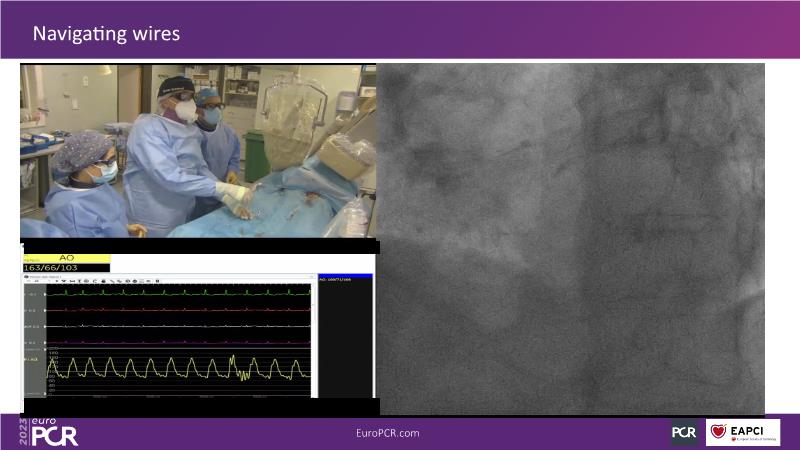

Discover the indispensable toolset of ultra-low contrast (ULC) percutaneous coronary intervention (PCI) in complex coronary interventions and higher-risk patients in this session. Gain a comprehensive understanding of how ULC PCI can enhance the safety and quality of revascularization in complex procedures and learn practical aspects from recorded cases, including specific approaches utilizing intracoronary imaging, physiology, and dedicated tools and techniques.

- To learn practical aspects from recorded ULC PCI cases, including specific approaches using intracoronary imaging, physiology and dedicated tools and techniques